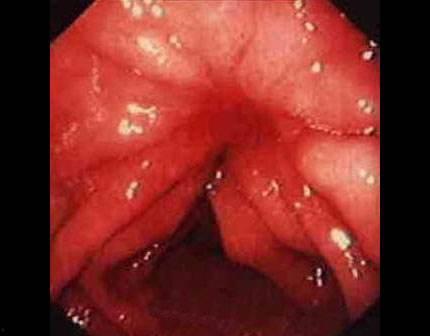

你知道嗎,胃炎是一種常見的胃部疾病,主要是因為胃黏膜受到刺激或損傷引起的。吃瓜的時候,我們往往喜歡邊吃邊說笑,這樣很容易導致吞咽過快,瓜籽、瓜皮等硬物刺激胃黏膜,引發胃炎。

據《中國慢性胃炎診療指南》顯示,我國慢性胃炎的患病率高達30%以上,而且這個數字還在逐年上升。我那胃疼得簡直要了我的命,真是后悔當初貪嘴??!